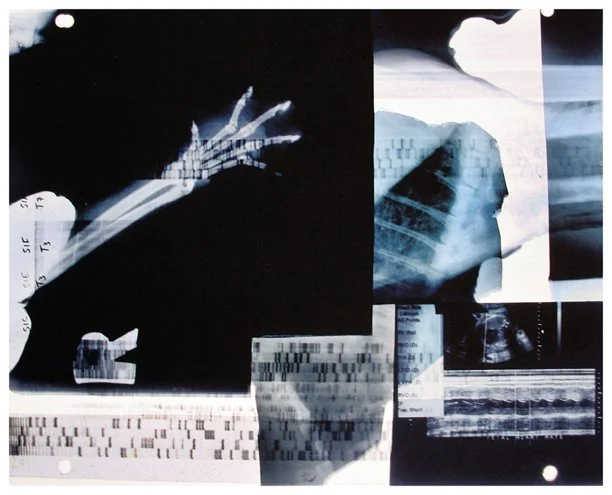

Insight is a series of collaged X-ray fragments, which were digitally composed into giclée prints. They speak not only of the body’s interior, but of the human experience it contains.

Drawn from DNA sequencing gels, mammograms, ultrasound scans, and cell cultures grown in Petri dishes, these compositions reframe diagnostic materials as metaphoric landscapes. What once served to identify illness becomes a language of line, texture, and light. They serve as a quiet meditation on fragility, resilience, and the unseen forces that shape us.

Each image in Insight is both an anatomical artifact and an artistic inquiry. Each one is part of my ongoing exploration of the relationship between Art, Science, and Medicine. Through digital layering and compositional play, I aim to dissolve the boundary between clinical detachment and emotional intimacy by inviting viewers to look inward and find meaning in the microscopic.